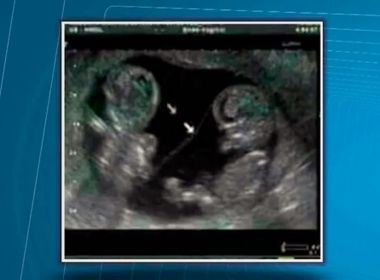

Uma mulher que teria dado luz à gêmeos em 24 de junho, afirma que um dos bebês desapareceu em uma maternidade de Ilhéus, região sul do estado. Dona de casa, Cleidiane Silva dos Santos, relatou à delegada substituta Andrea Oliveira, que as ultrassonografias realizadas durante a gravidez, inclusive a última feita no dia 03 de junho, confirmavam que ela tinha gêmeos. Quando ela deu entrada na Maternidade Santa Helena, anexo ao Hospital São José para realizar o parto, uma enfermeira teria avaliado e informado que estava tudo bem com os gêmeos. “Ela falou bem assim: os dois está (sic) bem, porque ela já tinha olhado no negócio [ultrassonografia] que eram dois gêmeos. Ela falou ’tá bem’ (sic). Aí ela mandou tomar um banho e ela mandou ir para a sala de parto”, afirmou a mãe ao G1. No momento da cesárea, Cleidiane relata ter passado mal e caído no sono. “Eles chegaram com uma criança, ainda no outro dia, porque o neném ficou cá embaixo, no berçário. Eu falei: cadê o outro? Aí ele falou bem assim: ‘mas só tinha um’. Eu falei não, porque eu vim para a maternidade para ganhar dois e eu estou aqui com o ultrassom, e eu escutei o coração dos dois lá embaixo, e ela [a enfermeira] falou que os dois estava (sic) bem. E como é que vocês aparecem aqui com uma criança só?”, disse. O caso está sendo investigado pela Delegacia Territorial de Ilhéus. “Estamos apurando se a ultrassonografia está errada e ela só tinha um bebê ou se o sumiço ocorreu na maternidade”, informou Andréa Oliveira. Segundo a titular, a polícia solicitou o prontuário, o nome completo da equipe que atendeu Cleidiane e já entrou em contato o médico que fez o ultrassom em que constavam os dois bebês. “Chamaremos todos para depor. Entramos em contato com o diretor do hospital, mas até agora estamos aguardando resposta”, disse. Apesar de o parto ter ocorrido no dia 24, Cleidiane só conseguiu ir à delegacia realizar a queixa na primeira semana de julho. “Ela foi à maternidade ter a criança sozinha, o pai do bebe bebê está preso, ela não tem auxílio dos familiares. Como teve uma complicação no parto ela passou uma semana internada e diz só ter conseguido vir agora”, falou. Abalada, Cleidiane explicou ao G1 que está com sentimento “De revolta e de tristeza, porque eu não posso fazer nada”.